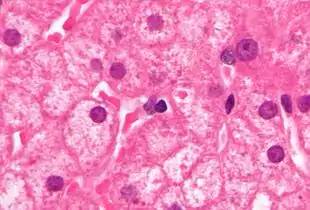

Micrograph showing ground glass hepatocytes. H&E stain.

Micrograph showing ground glass hepatocytes. H&E stain. Micrograph showing ground glass hepatocytes. H&E stain.

Micrograph showing ground glass hepatocytes. H&E stain. Micrograph showing ground glass hepatocytes. H&E stain.